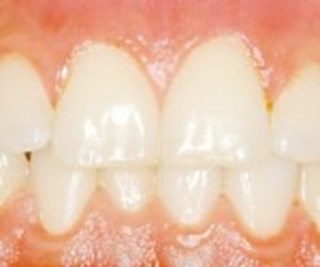

Ett inflammerat tandkött kan se helt friskt ut.

En inflammation i tandköttet kan vara början till parodontit. Och det är placket som bildas i munnen som är orsaken till tandköttsinflammation (gingivit). Inflammation utan parodontit är enkel att behandla. Med förbättrad munhygien läker det oftast ut på en eller ett par veckor. Dock kan inflammationen komma tillbaka snabbt om munhygienen försämras. Noggrann rengöring med tandborste, tandtråd eller liknande är det enklaste knepet för att undvika inflammerat tandkött.